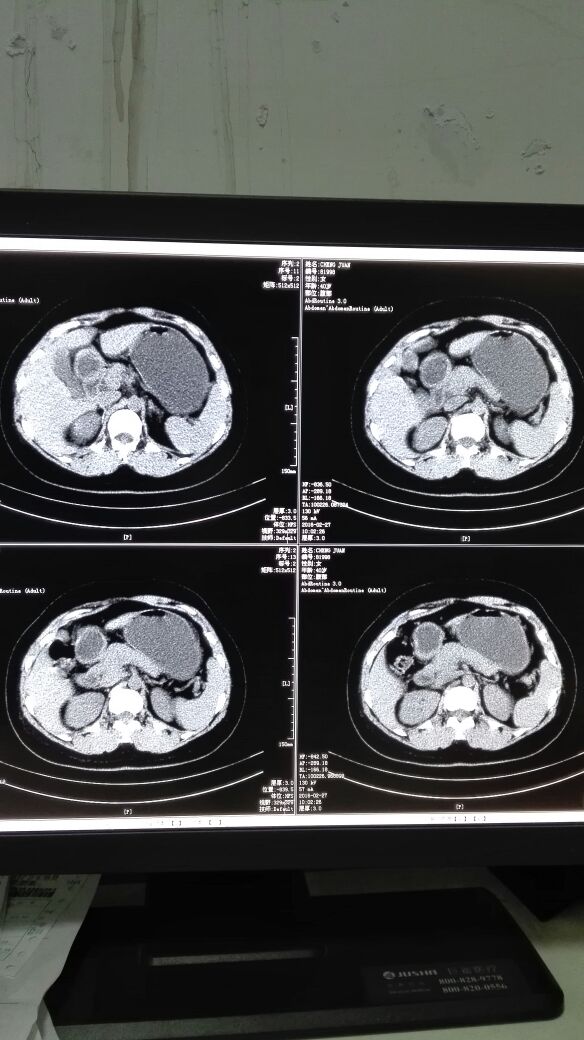

患者女,40岁,医院职工家属。B超体检时发现肝肾间多发囊性占位性病变。行腹部平扫示:右肾上腺区囊性占位,有分割和钙化点,右肾受压下移。诊断意见:右肾上腺囊腺瘤可能性大,建议进一步检查明确。后到市级医院检查并切除手术,病理切片考虑肾上腺囊肿。今腰部不适复查CT片。